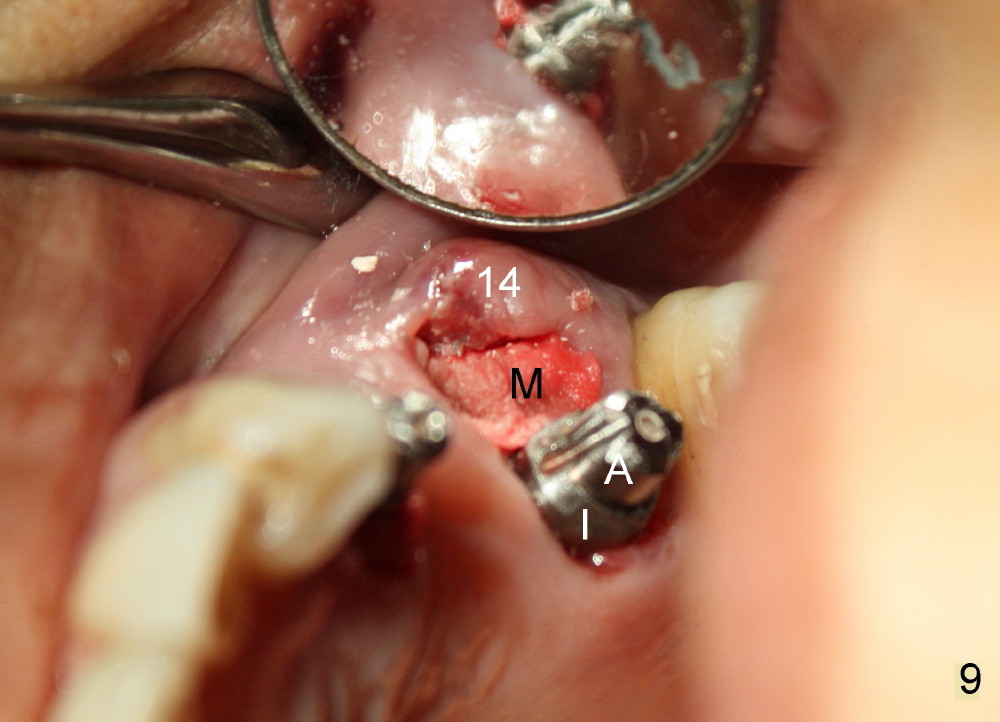

Buccal to #14 implant/abutment is a large defect, which is filled with allograft and Osteogen and covered by collagen membrane (Fig.9 M). The defect at the site of #12 is mesiopalatal, which is repaired in the same fashion (Fig.10: M). The collagen membrane is in turn protected by the "overhang" (extension) of the immediate provisional bridge (Fig.11,12 *). Once the wounds heal (Fig.13, 9 days postop), the extension is trimmed (Fig.14).